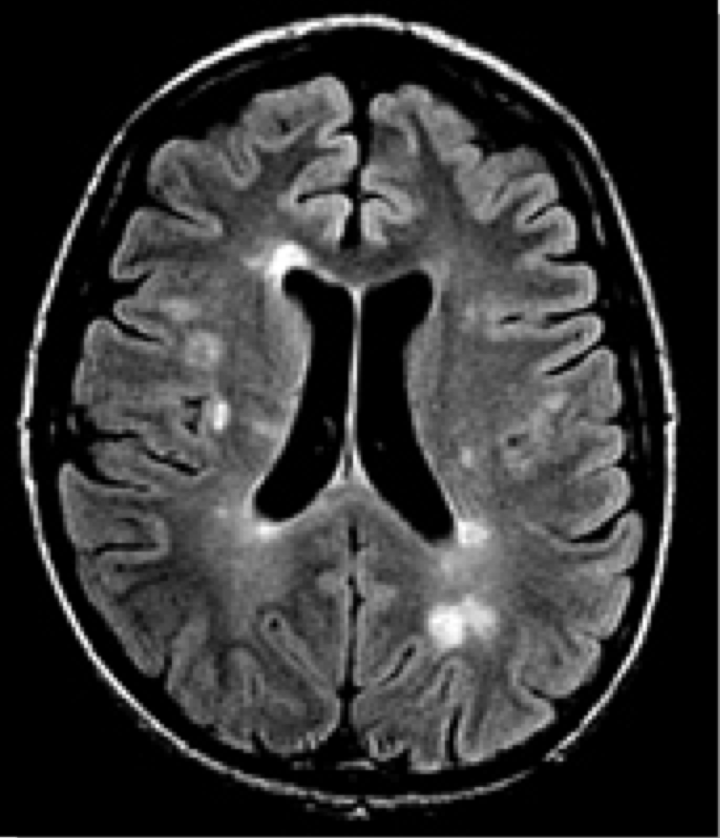

Exames de Imagem

incluir as imagens e as caracteristicas de em